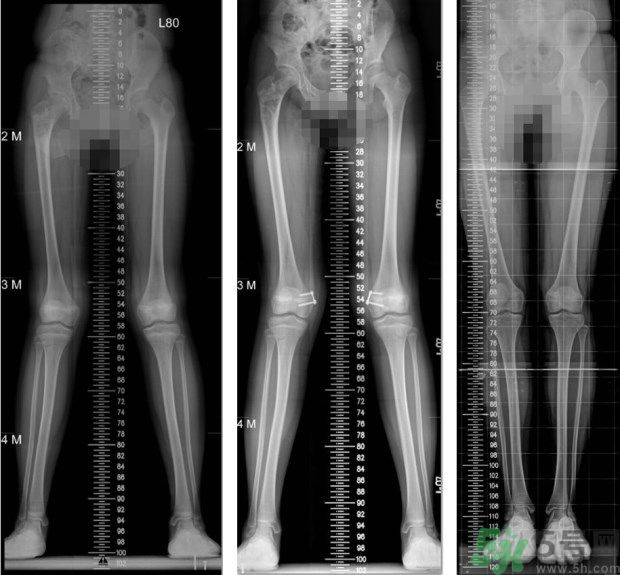

左圖:矯正前,4歲女童,左小腿外側(cè)的生長板過度發(fā)育,導(dǎo)致左腳O型腿;中圖:矯正中,在左小腿外側(cè)的生長板,夾上小夾子,矯正過度發(fā)育的生長板;右圖:矯正後,經(jīng)過1年的生長板導(dǎo)引治療,恢復(fù)正常的外觀。(照片提供:王廷明 醫(yī)師)

左圖:矯正前,11歲女童,大腿內(nèi)側(cè)的生長板過度發(fā)育,導(dǎo)致雙腳X型腿;中圖:矯正中,在大腿內(nèi)側(cè)的生長板,夾上小夾子,矯正過度發(fā)育的生長板;右圖:矯正後,經(jīng)過8個月的生長板導(dǎo)引,恢復(fù)筆直的雙腳。(照片提供:王廷明 醫(yī)師)